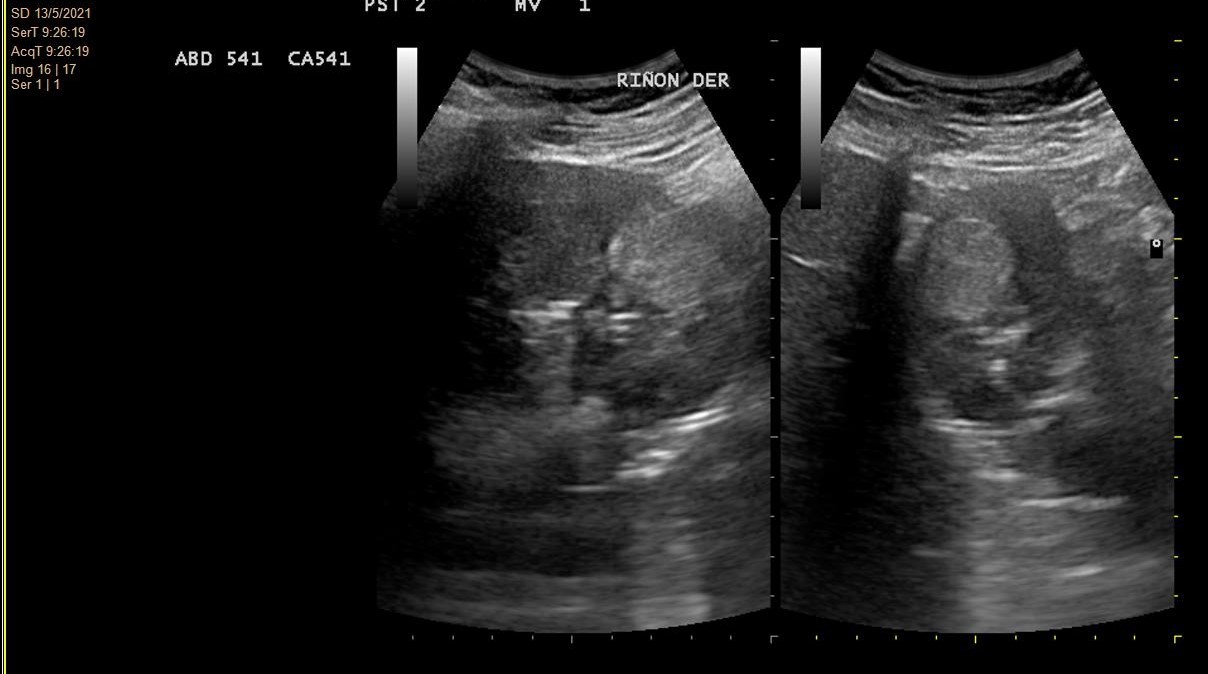

- Hallazgos ecográficos (mayo 2021): Imagen hiperecogénica redondeada de 2,9 cm de diámetro, de ecogenicidad irregular, localizada en tercio medio-distal del riñón derecho, sin evidenciarse litiasis o hidronefrosis.